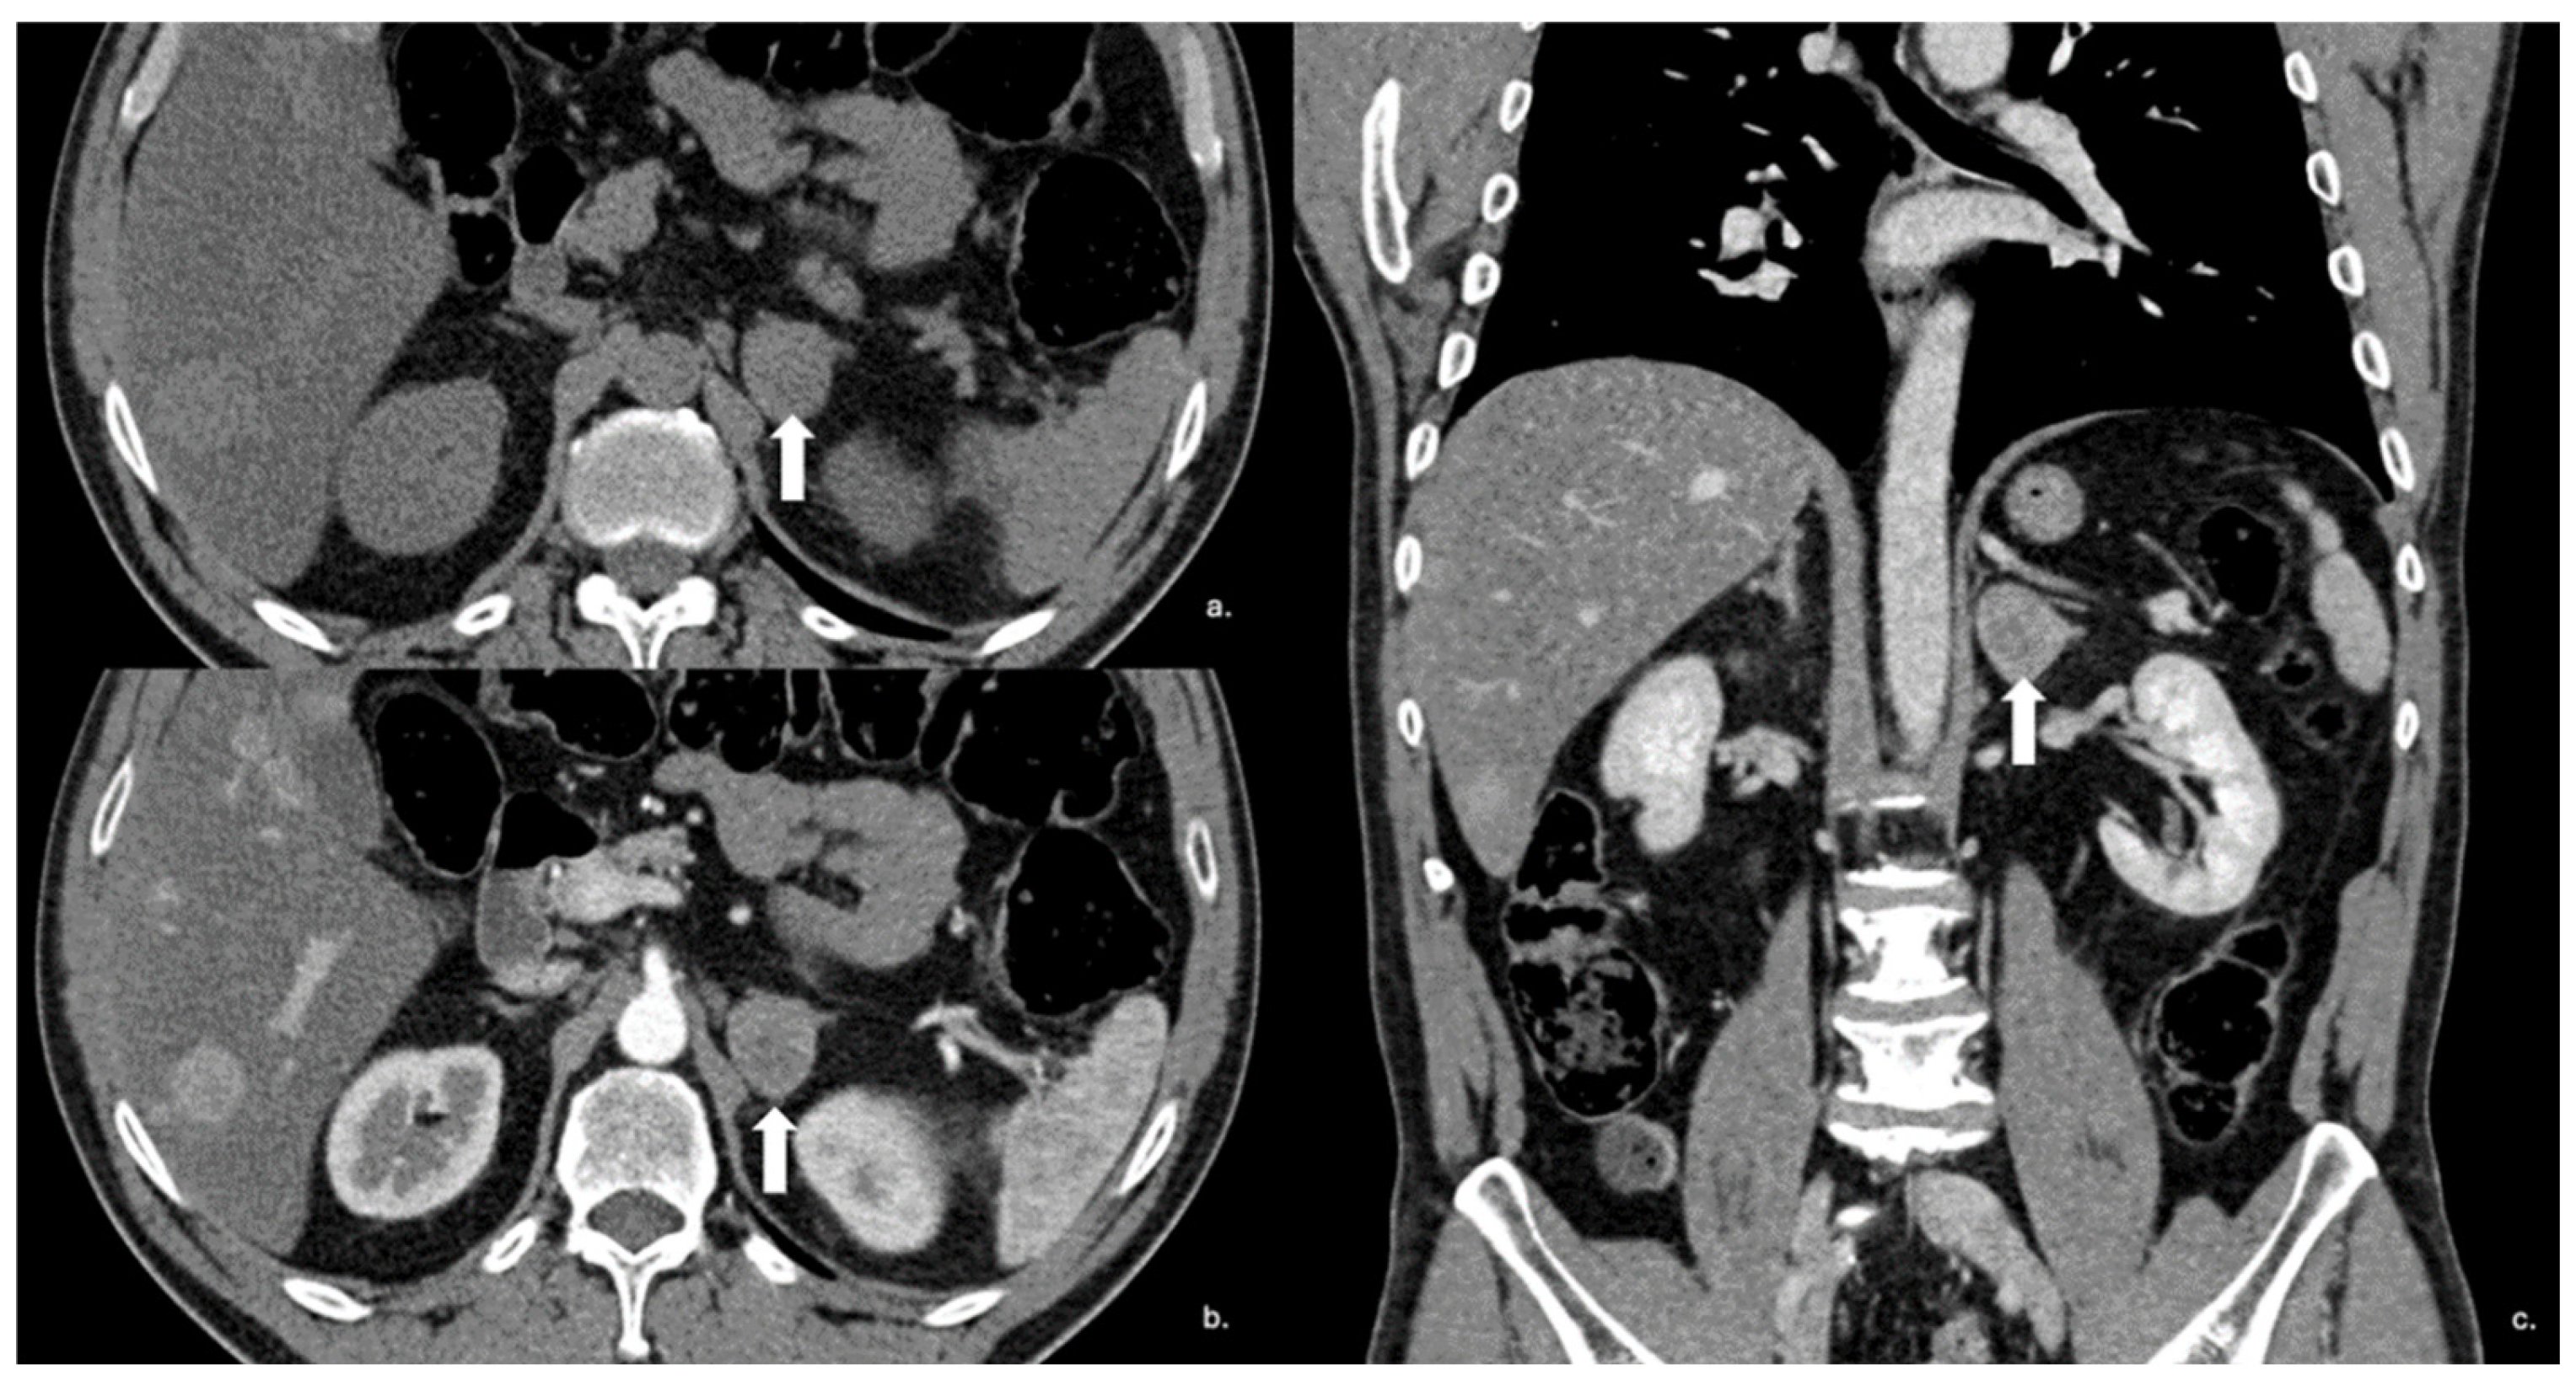

Figure 14.

Axial unenhanced (a), arterial (b), and coronal venous (c) CT phases show a lung carcinoid metastasis (arrow) of the left adrenal gland. Additional hypervascular metastasis can be seen in the liver, particularly in the arterial phase.